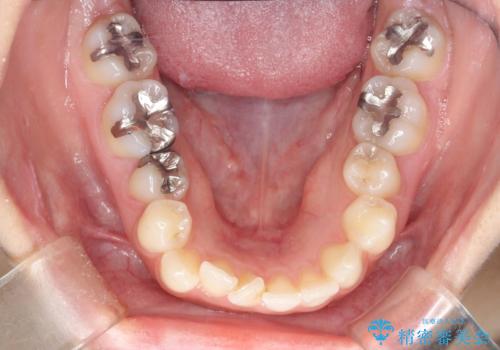

- 口元が出てるのが気になるとのことで来院されました。

上下左右前から4番目の歯を抜歯して前歯を後方に下げて、口元を下げる計画としました。